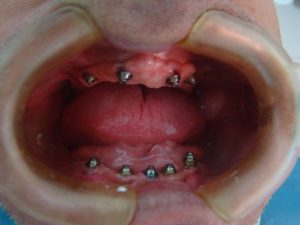

Veja os resultados de nossos pacientes

Implantes dentários são suportes ou estruturas de metal (normalmente de titânio) posicionadas cirurgicamente no osso maxilar abaixo da gengiva para substituir as raízes dentárias. Uma vez colocados, permitem ao dentista montar dentes substitutos sobre eles.